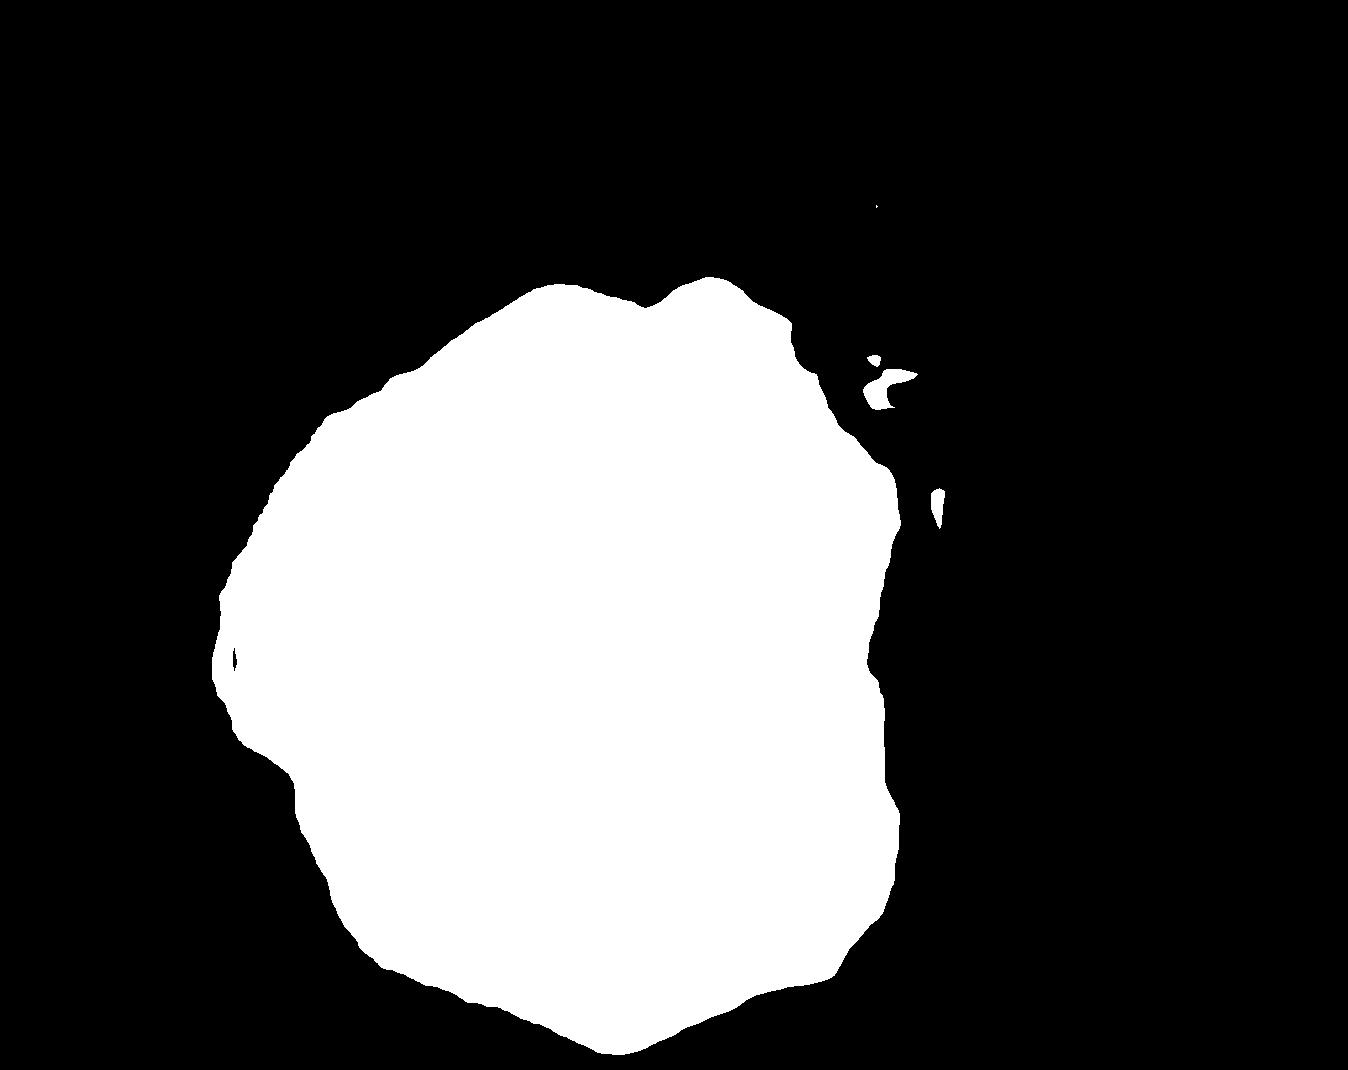

Figure 4 shows some example masks predicted by our best performing model (DivergentNets) together with masks produced by the intermediate models. We see that each intermediate model learns slightly different features, making an overall more precise segmentation mask when combined. For example, the first row of Figure 4 shows the predicted masks and ground truth of a large polyp. We see that each model predicts slightly different masks for the same input and that TriUNet over-estimates the size of the polyp. After averaging the predicted masks for DivergentNets’ final output, this area is smoothed out by the predictions from the other intermediate models.

Even though DivergentNets primarily produces more accurate masks than any single model, there are cases where masks from the intermediate model better match the ground truth. We see this in row three, where DeepLabv3+ produces a more precise mask than all other intermediate models, making the averaged output less accurate.